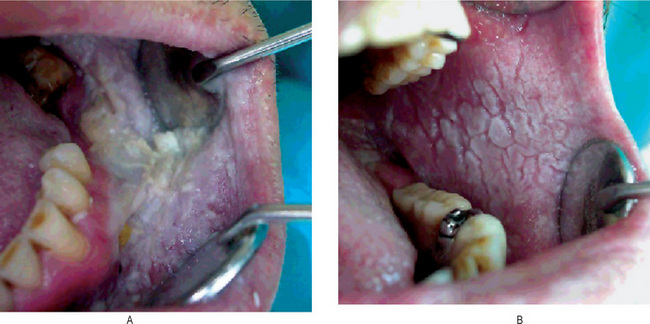

The oral mucosa is probably more commonly involved than is generally realized, according to Gorlin and Chaudhry, who found a number of reports of oral lesions in the literature. In addition, they pointed out that other mucosal surfaces such as vulva, pharynx and larynx have also been reported as sites of the disease. Mucosal lesions have been said to be apparent only when there is extensive skin involvement. However, Weathers and Driscoll have stated that severe skin involvement is not necessary for the occurrence of oral lesions, although the severity of oral involvement did tend to parallel that of the skin. Nevertheless, oral involvement has been reported in as high as 50% of all cases.

The oral lesions appear as minute, whitish papules which feel rough upon palpation. Some cases have been described as rough, pebbly areas with verrucous white plaques or as having a cobblestone appearance as in the cases of Weather and his associates and Prindiville and Stern. These are most frequently found on the gingiva, tongue, hard and soft palates, buccal mucosa and even the pharynx (Fig. 19-15).

The disease is misnamed, since the changes are not restricted to the hair follicles. The characteristic findings in skin lesions are hyperkeratosis, papillomatosis, acanthosis and a peculiar benign dyskeratosis. This benign dyskeratosis is characterized by rather typical cells called corps ronds and grains. The corps ronds are larger than normal squamous cells and have a round, homogeneous, basophilic nucleus with a dark eosinophilic cytoplasm and a distinct cell membrane. These are found usually in the granular layer and superficial spinous layer. The grains are small, elongated parakeratotic cells situated in the keratin layer. Both corps ronds and grains represent partially keratinized cells and are found also in the typical slit-like intradermal vesicle just above the basal layer of cells, the typical suprabasilar cleavage. Acantholytic cells are commonly found floating in the lacunae produced by this intraepithelial separation. The microscopic features of the oral lesions are identical except that the hyperkeratotic changes are generally not pronounced.